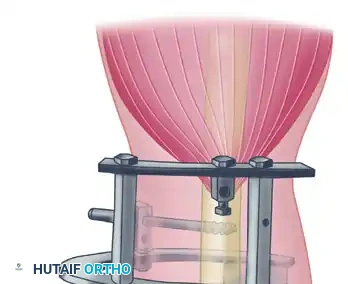

3. Ligament Reconstruction (The Arafiles Technique)

In cases of profound instability where dynamic fixation is unavailable or insufficient, surgeons may opt for ligament reconstruction with or without adjunctive fixation. The Arafiles technique utilizes a tendon graft routed through precisely drilled osseous tunnels to recreate the stabilizing vectors of the collateral ligaments.

The following sequence illustrates the complex reconstruction for an old posterior dislocation of the elbow, demonstrating the slot created in the trochlea and the specific lines of drill holes (A to D) that dictate the course of the tendon graft.

Note the intact forearm flexor origin during the completed repair, which provides secondary dynamic stability to the medial aspect of the reconstructed joint.